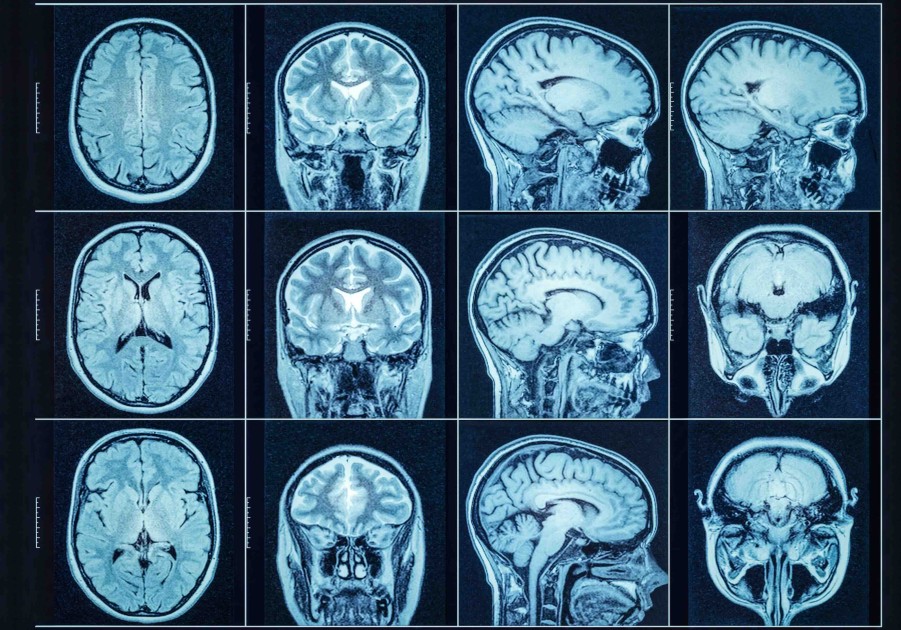

L’imagerie cérébrale peut-elle révéler si une personne est touchée par la dépression ? Cette question anime la recherche depuis de nombreuses années. Des modifications de la structure cérébrale ont bien été observées chez les patients dépressifs, ce qui laisse penser que l’IRM structurelle pourrait, un jour, aider les médecins à mieux comprendre et diagnostiquer cette maladie. Dans le cadre d'une collaboration internationale entre des équipes de l'Institut de biosciences moléculaires (IMB) de l'Université du Queensland, en Australie, de l’Institut du Cerveau et de l’Hôpital Bicêtre à Paris, les chercheurs ont mis cette hypothèse à l’épreuve. Ils montrent que l’imagerie de la matière grise fournit des indices utiles, mais ne constitue en aucun cas un outil diagnostique. Leurs résultats sont publiés dans la revue Translational Psychiatry.

L’équipe internationale, formée grâce à la collaboration entre l’Institut du Cerveau et l’Université du Queensland, en Australie, a analysé les IRM cérébrales de près de 8 000 personnes enregistrées dans l’UK Biobank, dont environ 1 500 présentaient des antécédents de trouble dépressif majeur. À l'aide de modèles informatiques avancés, les chercheurs ont entraîné des algorithmes sur de minuscules unités tridimensionnelles appelées voxels, l'équivalent 3D des pixels, à partir des images de la base de données. L’objectif ? Déterminer s’il existe des marqueurs d’imagerie capables d’identifier les personnes atteintes de dépression.